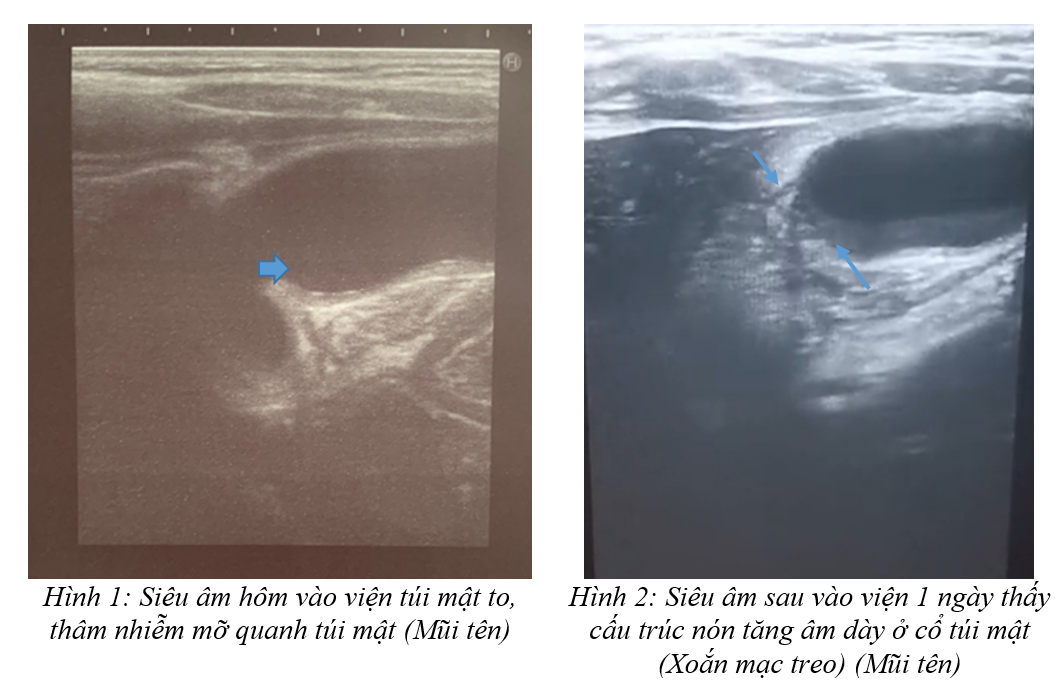

không chuẩn bị bình thường. Siêu âm lúc vào viện thấy túi mật kích thước

54x34mm, thành túi mật dày 3,2mm và có ít dịch ở giường túi mật; xung quanh túi

mật có thâm nhiễm mỡ, không thấy sỏi, không thấy u à TD

viêm túi mật (Hình 1). Siêu âm lần 2 sau khi vào viện 1 ngày thấy túi mật kích

thước 53x33mm, thành túi mật dày 3,1mm và giảm tưới máu, trong lòng túi mật có

ít bùn mật kèm ít dịch ở giường túi mật, xung quanh túi mật thâm nhiễm mỡ nhiều

hơn so với lần siêu âm trước. Đáy túi mật lệch sang trái so với giường túi mật

và đáy túi mật thay đổi khoảng cách so với giường túi mật khi thay đổi tư thế bệnh

nhân kèm đoạn cổ túi mật thấy cấu trúc hình nón tăng âm dày, ấn đầu dò vào đoạn

cổ túi mật thấy trẻ đau tăng lênà nghi ngờ xoắn túi

mật (Hình 2). CLVT thấy túi mật kích thước 53.5x22.8x31.5mm, thành túi mật

-

Túi mật nổi với cấu trúc hình nón phản âm (xoắn mạc treo) ở cổ túi mật.